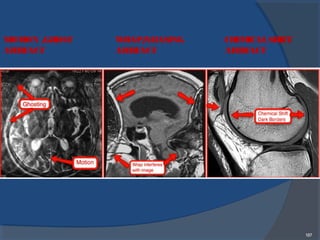

MOTION /GHOST

ARTIFACT

WRAP/ALIASING

CHEMICALSHIFT

188

1.Motion/Ghost artifact:

• Ghostsarereplicaof something in theimage.

•Originatesfrom any structurethat movesduring

acquisition of data.

Remedies:

2.Wrap around /Aliasing artifact :

•Objectsoutsideof theFOV overlap on theopposite

sideof theimage.

3. Chemical shift artifact or chemical shift

misregistration :

•It iscaused by thedifferent resonancefrequencies

between fat and water.

• Thiscreates very dark edgesbetween thetwo

along thefrequency encoding direction.